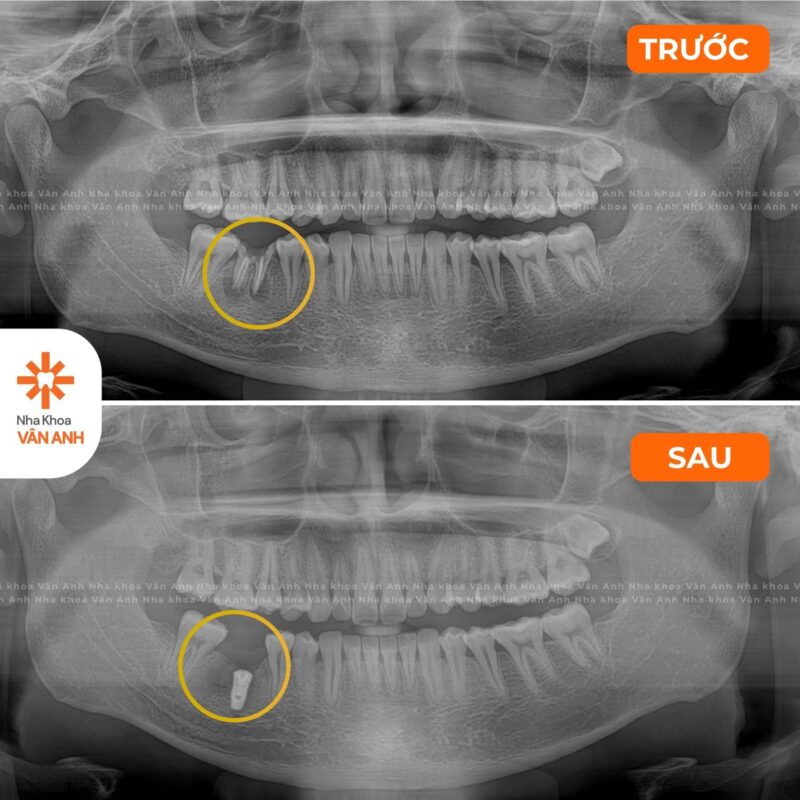

Lĩnh vực chuyên sâu: Phục hình – Tiểu Phẫu

- Chứng nhận Cấy ghép implant nha khoa cơ bản – Viện Đào tạo Răng Hàm Mặt, Đại học Y Hà Nội

- Chứng nhận Giải pháp ca nhổ răng khó – Implant cho xương xốp – Nâng xoang hạn chế ghép xương – Viện Đào tạo Răng Hàm Mặt, Đại học Y Hà Nội